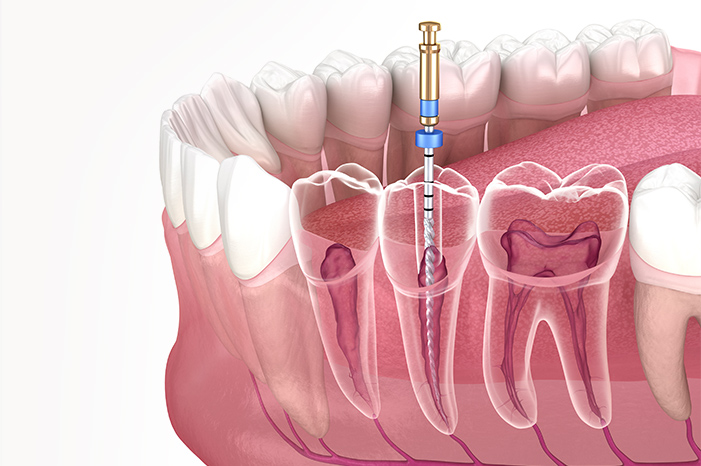

根管治療について

歯の痛みを根本から改善

抜かずに残すための治療

歯の内部にある神経が炎症を起こすと、強い痛みや腫れを引き起こします。根管治療は、その原因となる感染部分を丁寧に取り除き、歯を抜かずに残すための大切な治療です。当院では、清須市で地域に密着した診療を行い、再発を防ぐための精密な処置を徹底。拡大鏡などを活用し、神経の細い管までしっかり確認しながら、痛みを抑えた安心の治療を目指しています。

Nitiファイル

しなやかで折れにくいニッケルチタン製の器具を使用し、複雑な形状の根管にも柔軟に対応します。従来よりも安全性と精度が高く、歯を残すための治療が可能です。

根管拡大装置

根管内部の洗浄や拡大を効率的かつ精密に行える電動式モーターです。一定のスピードとトルクで操作できるため、歯への負担を軽減しながら安定した治療を実現しています。